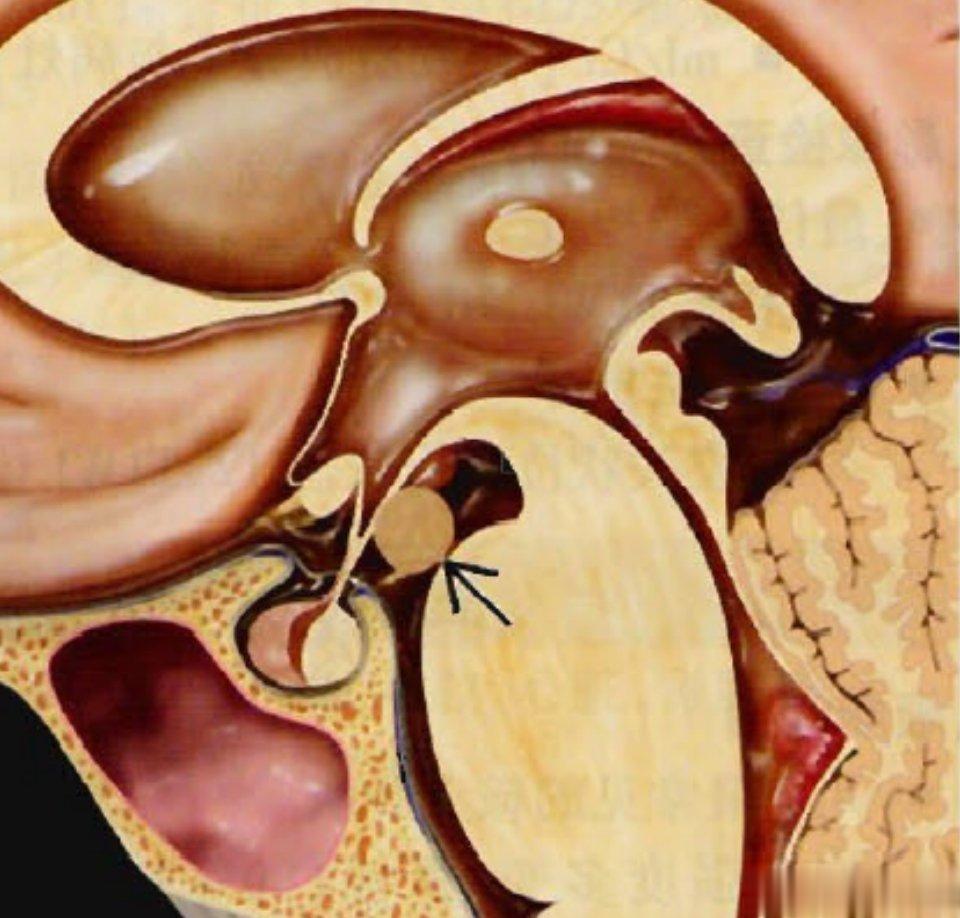

痴笑性癫痫的主要病因可分为:下丘脑错构瘤和额颞叶性癫痫两种。

下丘脑错构瘤又称灰结节错构瘤,为临床罕见的颅内先天性畸形,多发于儿童,主要表现为体内雌激素水平过高、第二性征发育早、骨龄增加及伴有无诱因的痴笑发作。

有专家认为下丘脑错构瘤起源于乳头体或灰结节,是正常脑组织形成的异位肿块,组成此种畸形的神经细胞类似于灰结节中的神经组织,并伴有正常胶质细胞。下丘脑错构瘤并非真正的肿瘤,没有生长性,但是能够严重影响儿童正常的身体发育。